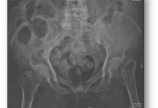

【骨质疏松】意外跌倒之后

病情概述: 李某,女,汉族,81岁,某厂退休工人,75kg。走平路时跌倒致左髋部疼痛、活动受限10天。患者10天前散步时,因躲闪对面行人不慎跌倒致左侧肢体着地,当即感到左髋部疼痛、站立和行走困难。摔倒时无昏迷、恶心呕吐、胸腹腰部疼痛二便失禁等。卧床休息数日后,疼… [详情]